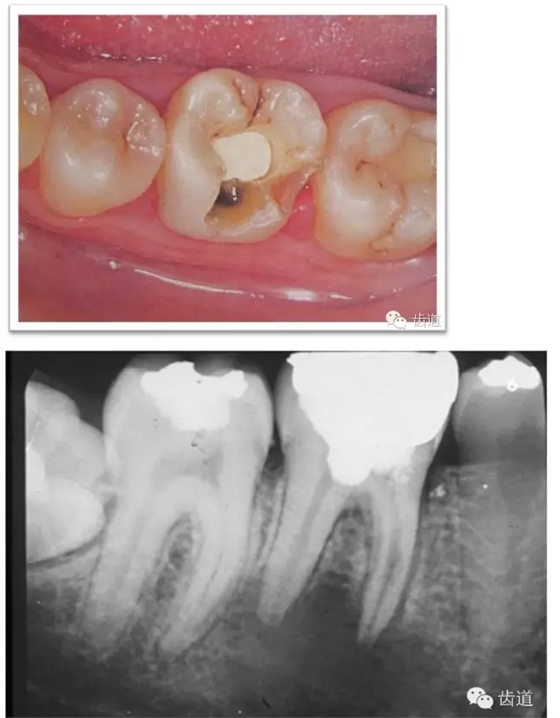

牙體預(yù)備時(shí)應(yīng)考慮的問題

l保護(hù)牙體組織

l基牙具有良好的固位形

l基牙具有良好的抗力形

l預(yù)留修復(fù)體的空間

l邊緣的適合性

l保護(hù)牙周組織

l多個(gè)基牙時(shí)就位道的調(diào)節(jié)

l實(shí)際備牙產(chǎn)生的問題

1. 保護(hù)牙體組織

l防止過度預(yù)備(造成牙髓激惹)

l保留活髓(保留牙體的整體性和韌性)

l過度預(yù)備抗力形喪失